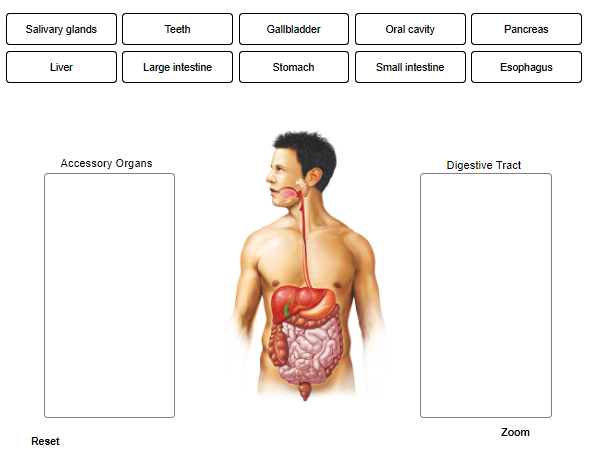

Label only the accessory organs of the digestive system.

Identify the roles of the asscessory organs and digestive tract